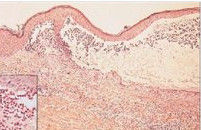

在BP的非大皰期或不典型患者,光鏡僅能看到表皮下裂隙和嗜酸性粒細胞性海綿水腫,很少能提供特異的信

息。在早期水皰的活檢標本,典型所見為表皮下皰、真皮上層嗜酸性粒細胞和單一核細胞的炎症浸潤。水皰內有纖維蛋白網和數量不等的炎症細胞浸潤(圖6),電鏡顯示形成的表皮下皰在透明板水平。

表皮下皰,真皮和皰腔內由嗜中性粒細胞和嗜酸性粒細胞組成的炎性浸潤。插入的圖片(高倍放大)顯示多數嗜酸性粒細胞的浸潤。